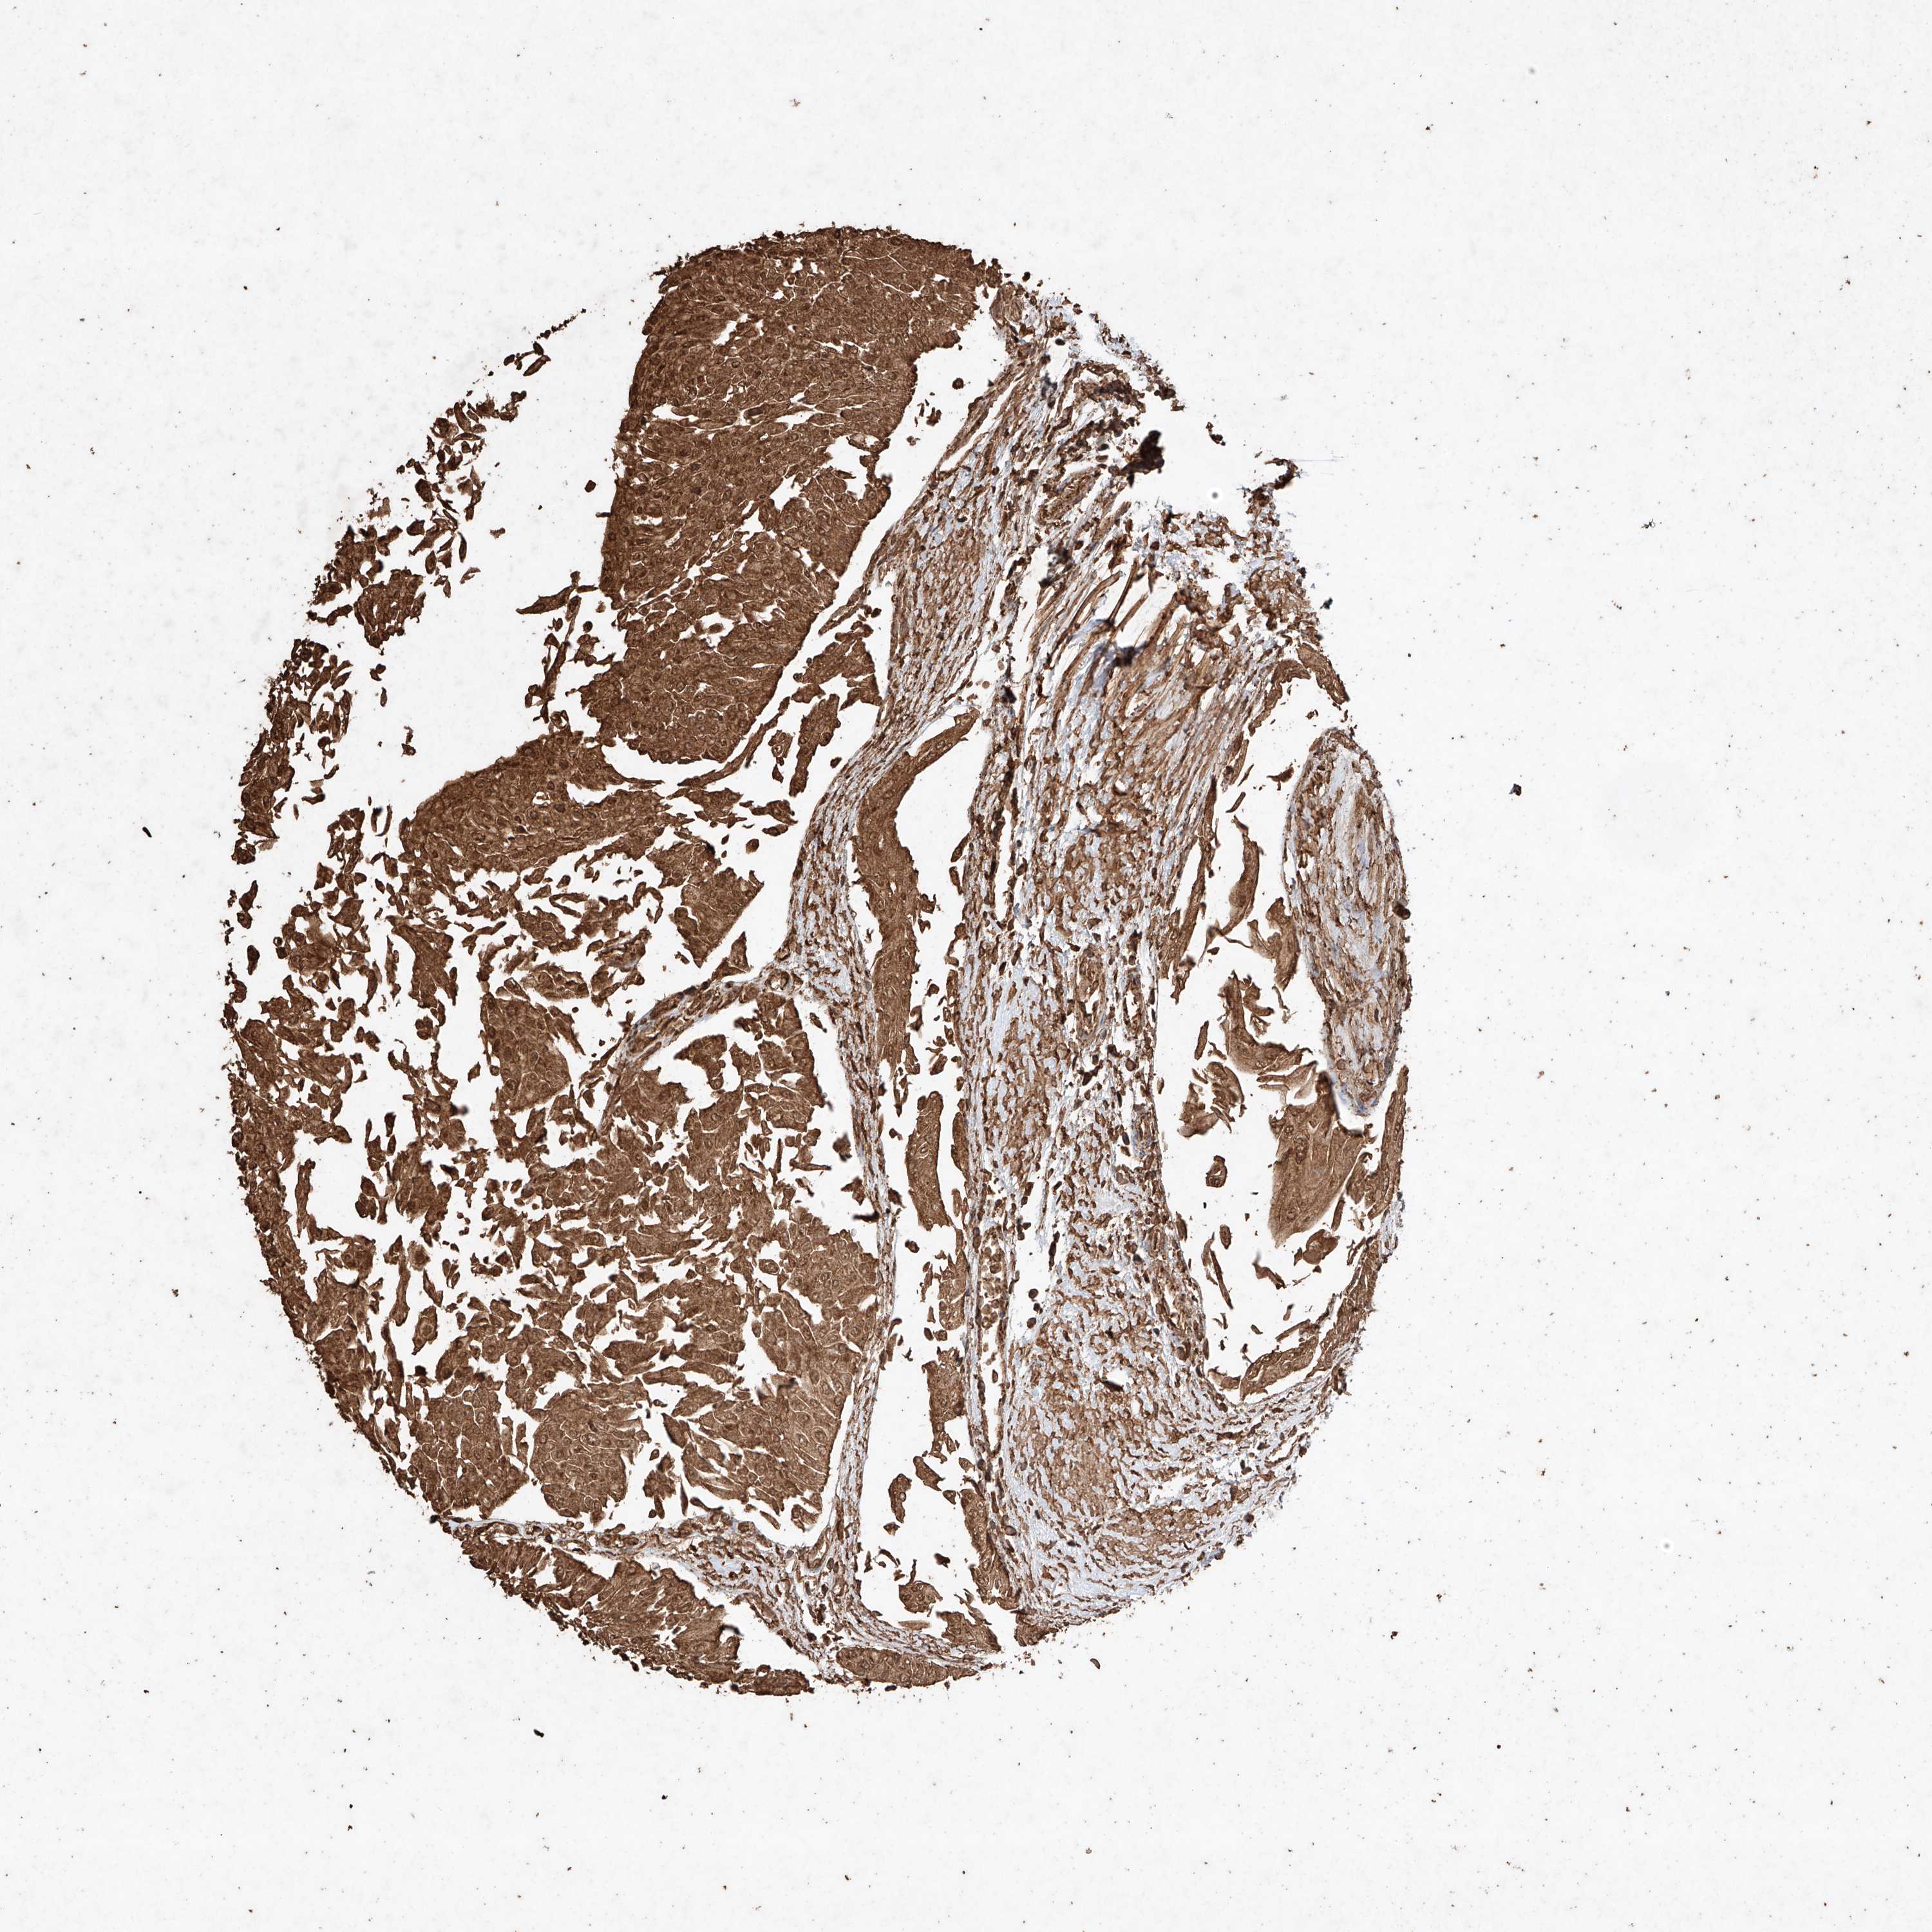

UROTHELIAL CANCER - Protein expressioni

A mouse-over function shows sample information and annotation data. Click on an image to view it in a full screen mode. Samples can be filtered based on level of antibody staining by selecting one or several of the following categories: high, medium, low and not detected. The assay and annotation is described here.

Note that samples used for immunohistochemistry by the Human Protein Atlas do not correspond to samples in the TCGA dataset.

Antibody stainingi

Antibody staining in the annotated cell types in the current human tissue is reported as not detected, low, medium, or high, based on conventional immunohistochemistry profiling in selected tissues. This score is based on the combination of the staining intensity and fraction of stained cells.

Each image is clickable and will lead to virtual microscopy that enables deeper exploration of all samples and also displays staining intensity scores, fraction scores and subcellular localization as well as patient and tissue information for each sample.

Antibody HPA040445

Antibody CAB034464

Urothelial carcinoma, High grade

Urothelial carcinoma, Low grade